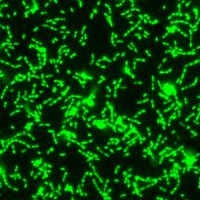

A fluorescent microscopy image of a S. mutans biofilm. Image courtesy of Nicole Kavanaugh of MIT and the American Society for Microbiology.

S. mutans attaches to teeth using sticky polymers that it produces, eventually forming a biofilm, a protected surface-associated bacterial community that is encased in secreted materials, according to lead author Erica Shapiro Frenkel, DDS, of Harvard University. As S. mutans grows in the biofilm, it produces organic acids as metabolic byproducts that dissolve tooth enamel, which is the direct cause of caries.

The starting point for dental caries is not the presence of S. mutans but the bacterium's firm attachment with tooth surfaces, Ribbeck explained.

"Once these microbes attach themselves to the surface of teeth, they grow in this location with a matrix, and once they form this community, this group of bacteria, they become really difficult to remove," she said.

They qualify as a biofilm, forming cells that are connected to each other by an extracellular matrix material that they secrete and surround themselves with.

"Once they are in this biofilm state attached to a tooth surface, then they become really difficult to remove, not only with a toothbrush but they also become resistant to clearance with mouthwashes," Ribbeck explained.

So it is this biofilm's attachment to teeth, not so much the presence of microbes, that causes caries.